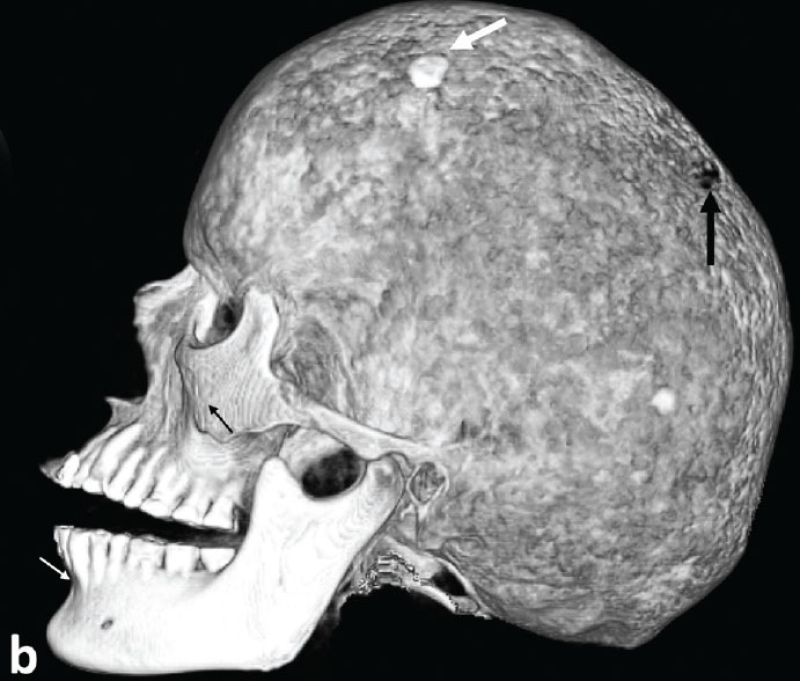

Görkem Arıca, İsmail Yılmaz, Doğu Küçüksüleymanoğlu, et al.

Arıca et al. reported that in fetuses with fetal growth restriction, decreased umbilical venous perfusion is accompanied by a compensatory increase in main portal vein flow, whereas the type of umbilicoportal anastomosis does not significantly affect main portal vein hemodynamics.